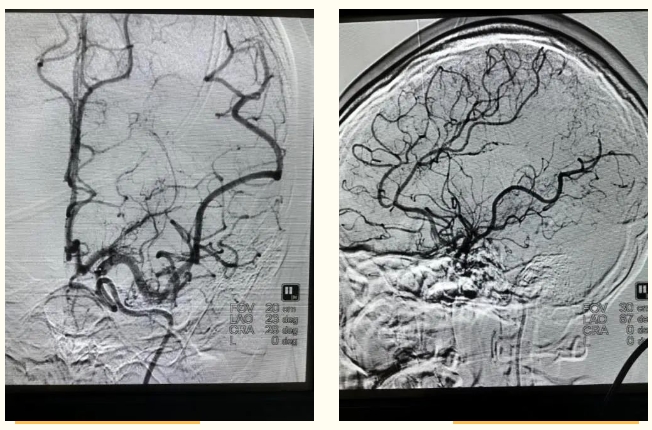

心脏病致脑梗死!神经外科团队让花季少女重获新生